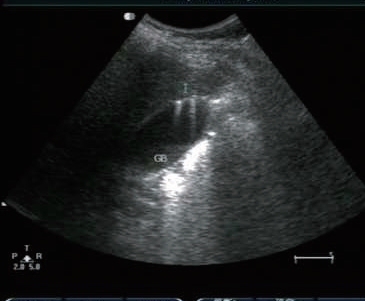

1)胆囊腔内高/强回声团。胆囊结石与周围液性胆汁声阻抗差较大,使得胆囊结石的边界可清楚显现。由于结石本身的形状、结构和成分不同,其回声形态可有较大差别。结构较致密且表面较光滑的结石,表现为新月形强回声(图5-6);结构较松散的结石,由于透声性好,结石的全貌均可被显示,呈满月形强回声(图5-7);数个堆积在一起的小结石可产生堆积状、沙堆状强回声(图5-8)。

图5-7 胆囊疏松结石(满月形)及声影

2)强回声团伴有声影。结石强回声后方,与声束入射方向一致的无回声暗带,即声影(图5-7)。它是结石对声能的吸收及反射的综合效应。典型的声影对确定胆结石比强回声更具有特异性。直径<0.3 cm的小结石,由于腹部探头声束波长产生绕射,声影不明显。